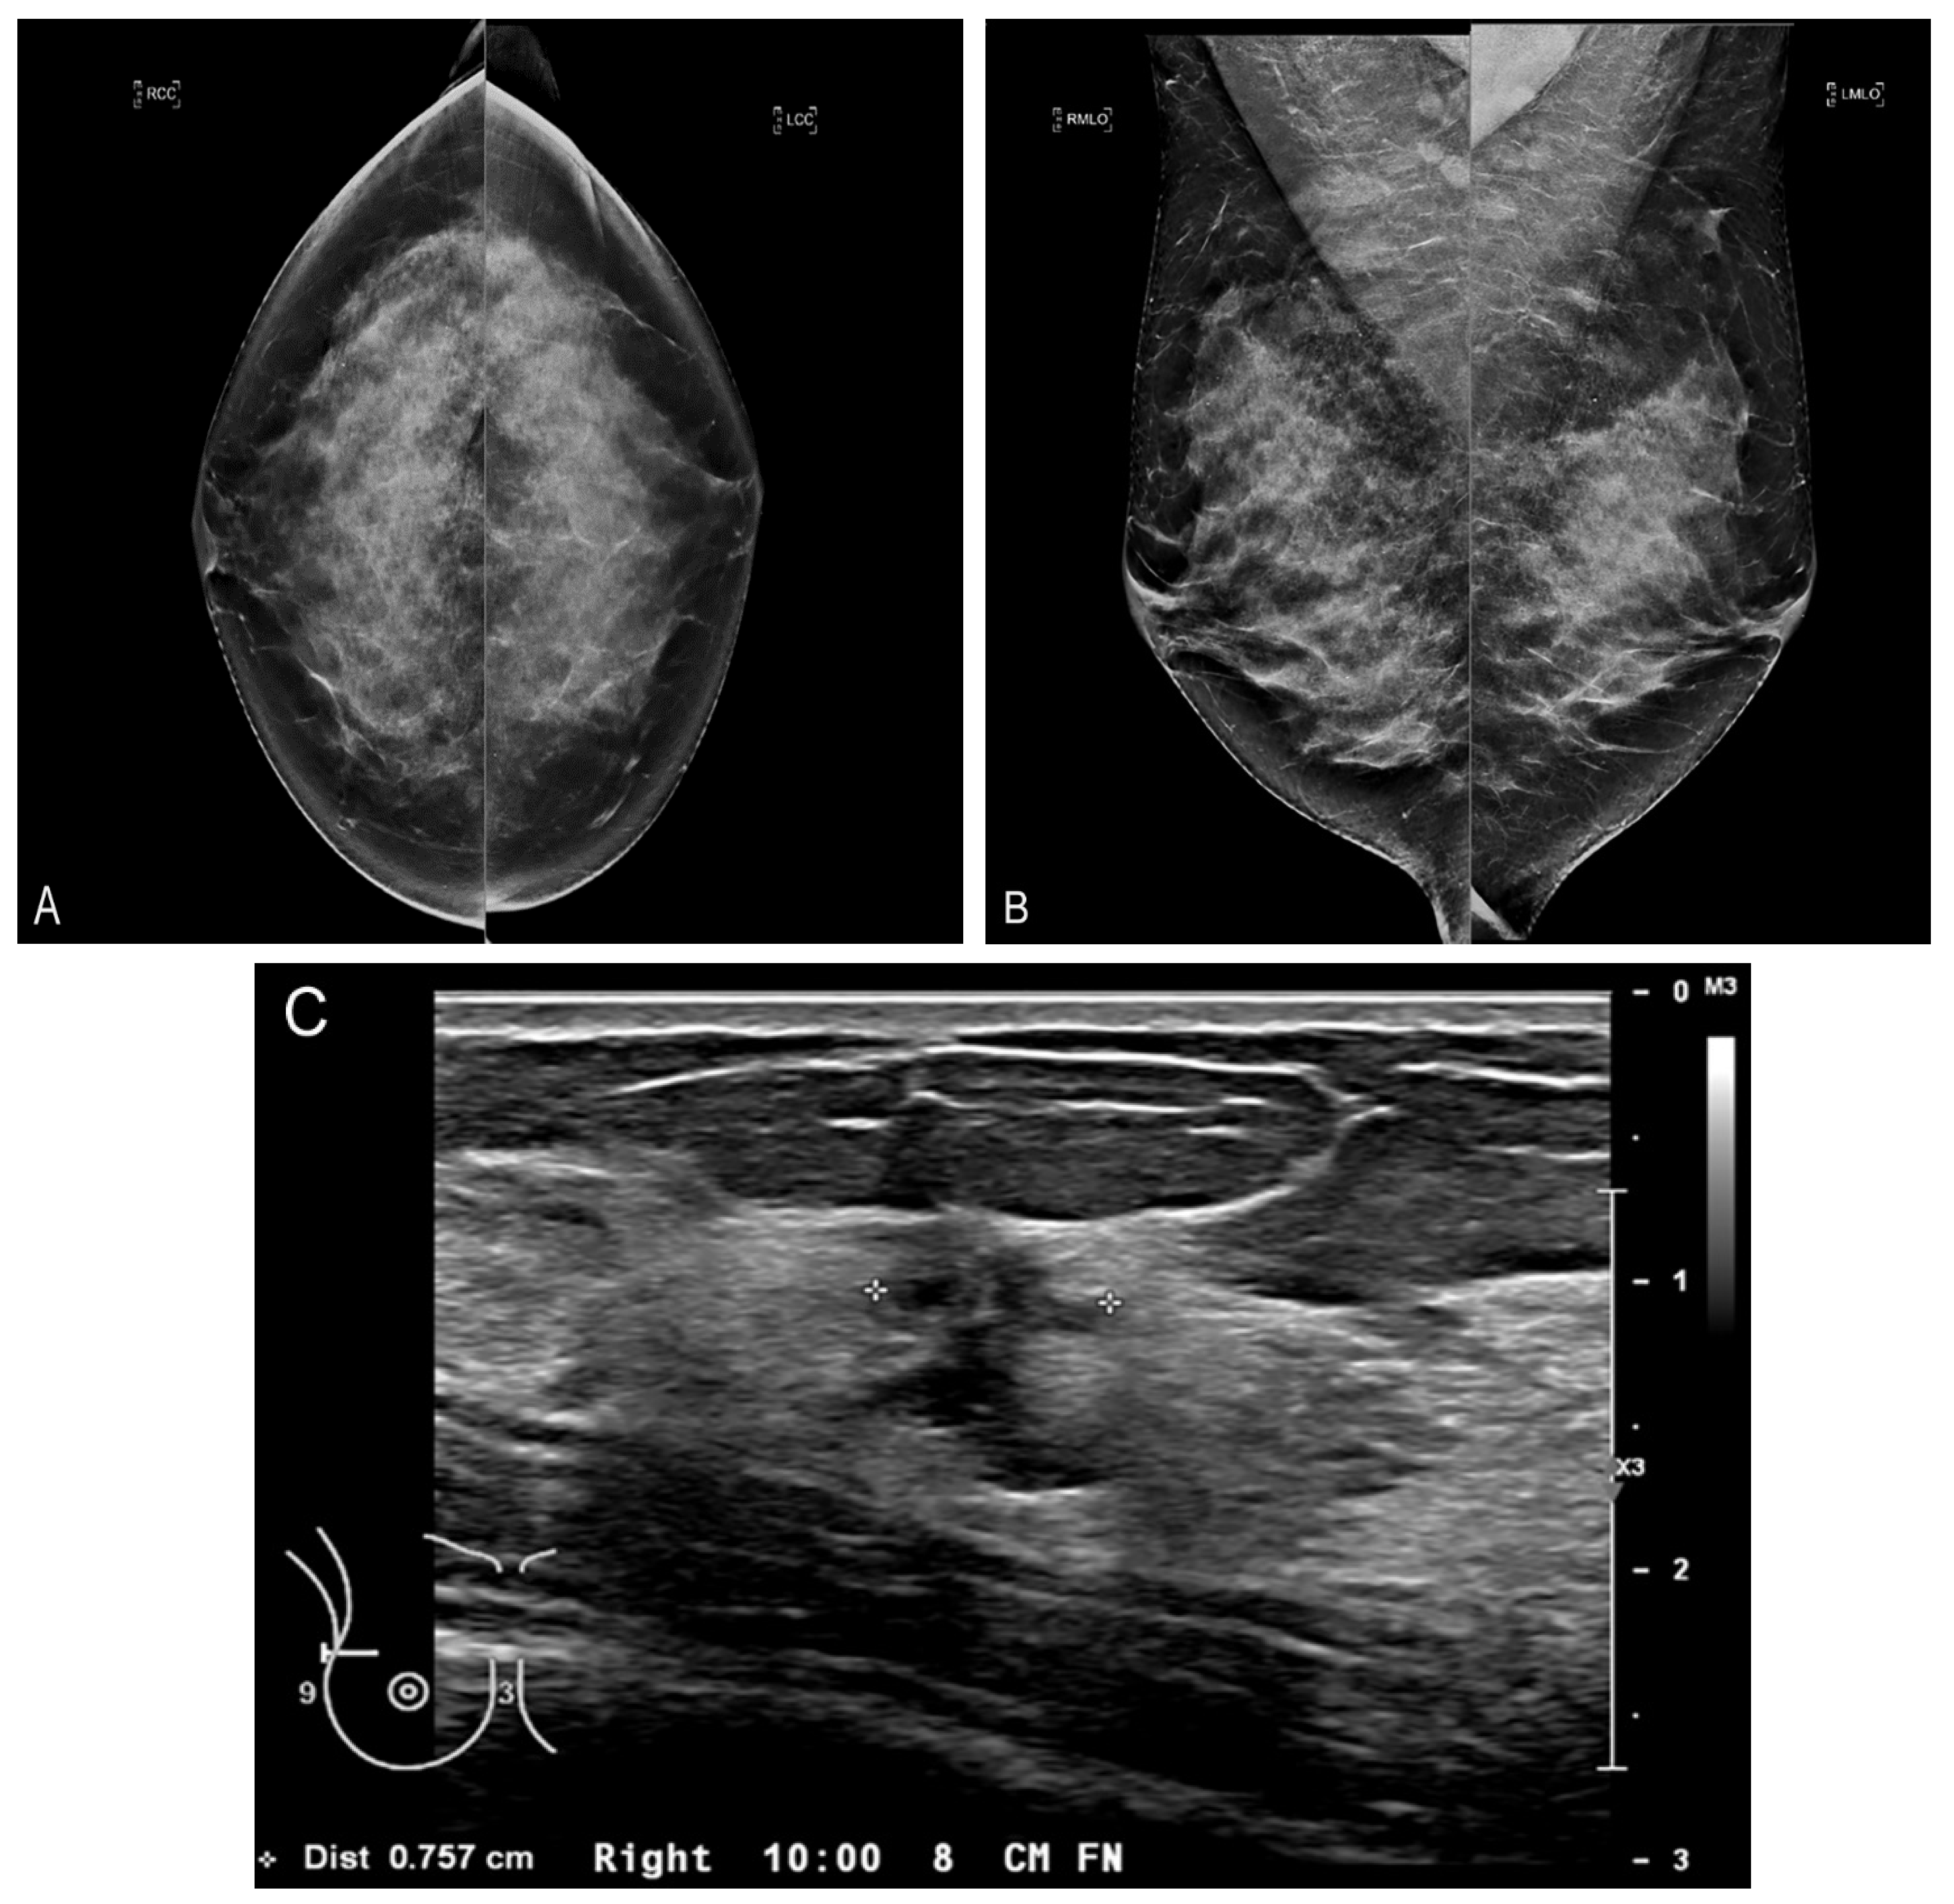

Figure 4.

Calcifications on CBBCT. Left CC (A) and MLO (B) views demonstrate pleomorphic micro-calcifications (arrow). (C) Unenhanced CBBCT images showing calcifications, which are marked with grid lines. (D) Contrast-enhanced CBBCT in the same patient showed an incidental mass marked with grid lines.